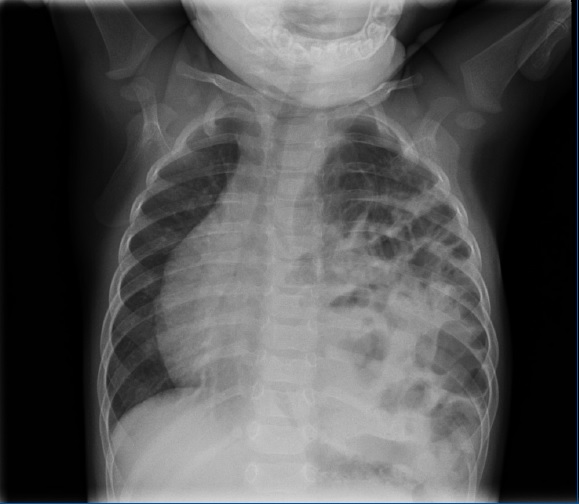

Se solicita radiografía de tórax, observándose una imagen compatible con hernia diafragmática (Fig. 1).

Figura 1. Ocupación de hemitórax izquierdo por estructuras aéreas que corresponden a asas intestinales en relación con una hernia diafragmática. Desplazamiento mediastínico. Hemitórax derecho sin áreas de consolidación